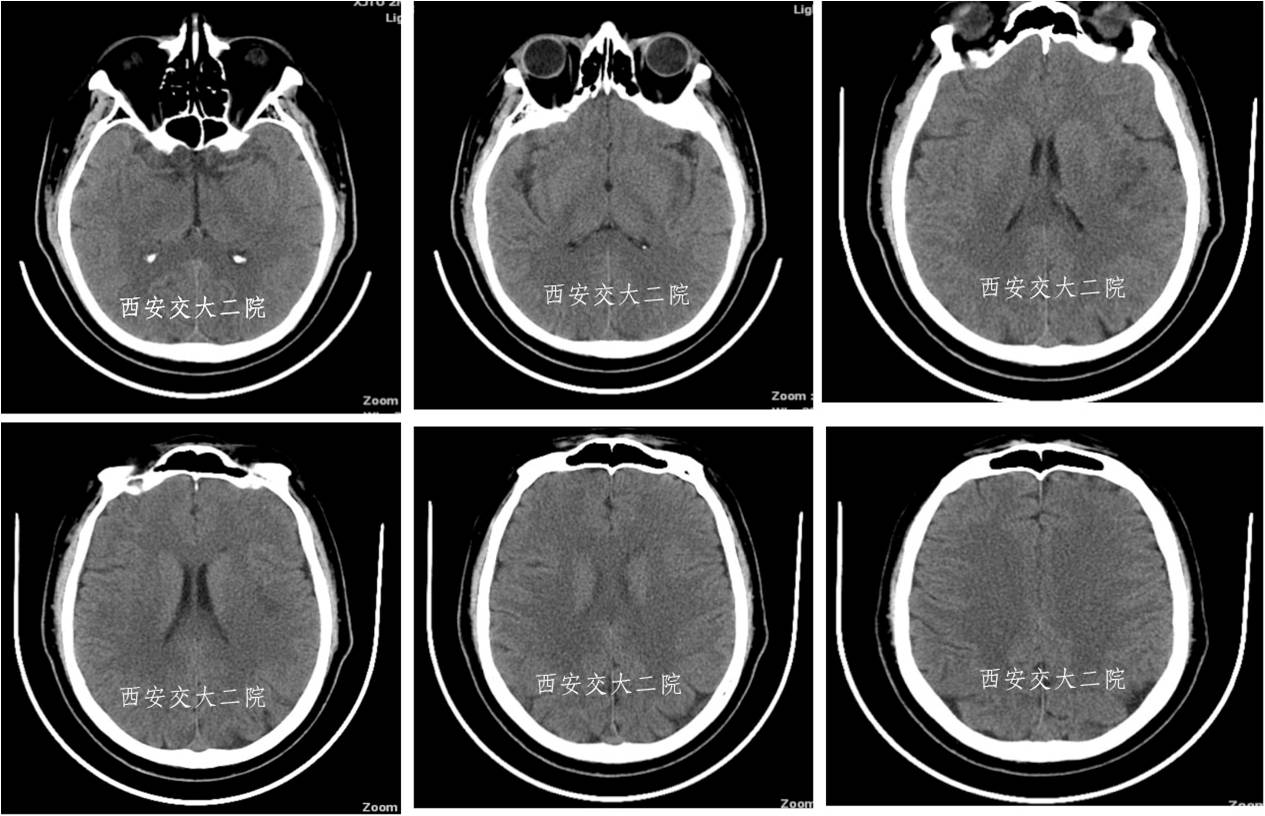

术前CT(病后1h)

术前DWI

术后即刻病情及脑CT

术后24小时脑CT